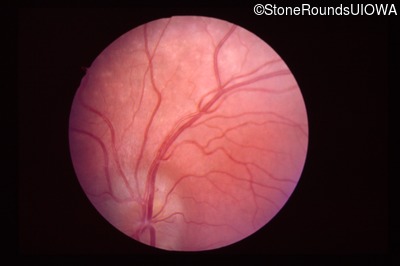

Visit at age: 7 years

Fundus Photography - Right - 20/40 -2

Exemplar